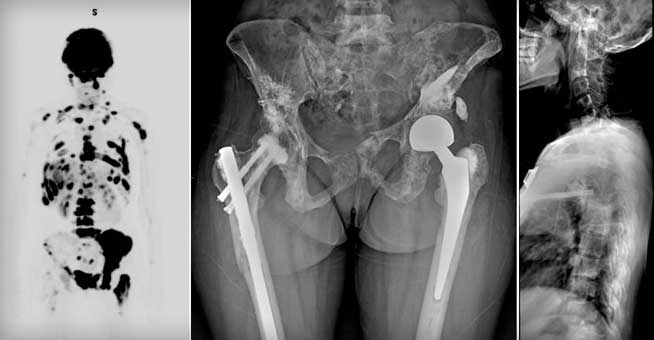

병기결정을 위해 시행하는 검사는

X-ray(가장처음), MRI, bonescan, chest CT, PET-CT, biopsy(마지막 검사) 등이 있습니다.